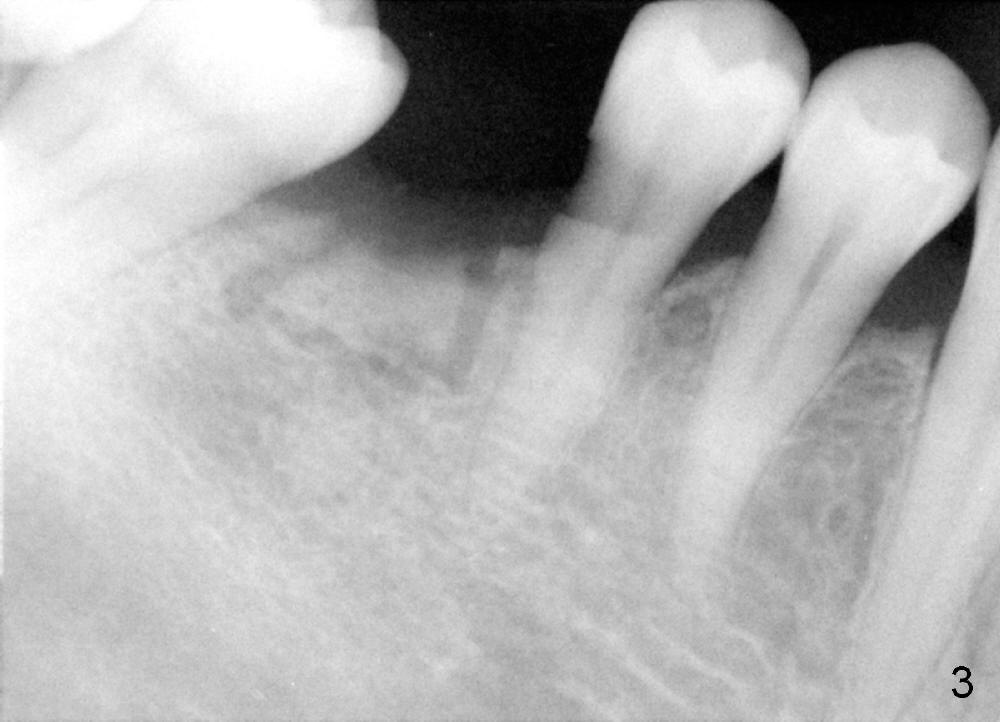

The ridge of the lower right molar is narrow buccolingually (Fig.1). After incision, ridge split is finished with a surgical fissure bur (Fig.2,3).